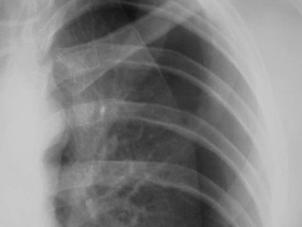

Traumatism toracic deschis Hemotorace stang masiv

Hemotorace stang masiv Hemotorace stang masiv

Hemotorace

drept masiv Hemotorace stang

Imagine CT Radiografie efectuata in ortostatism